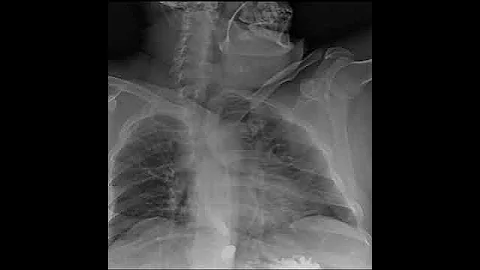

Dynamic X-ray Retrospective View Of The Esophagus In Motion | Konica Minolta Healthcare

Experience the incredible detail of Dynamic Digital Radiography (DDR) technology as we take a Retrospective look at the ...